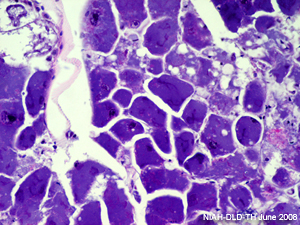

รอยโรคจำเพาะทางจุลพยาธิวิทยา |

- ทางจุลพยาธิวิทยา : พบรอยโรคจำเพาะคือ basophilic intracytoplasmic inclusion body ในเซลล์ไขมันการตรวจวินิจฉัย :